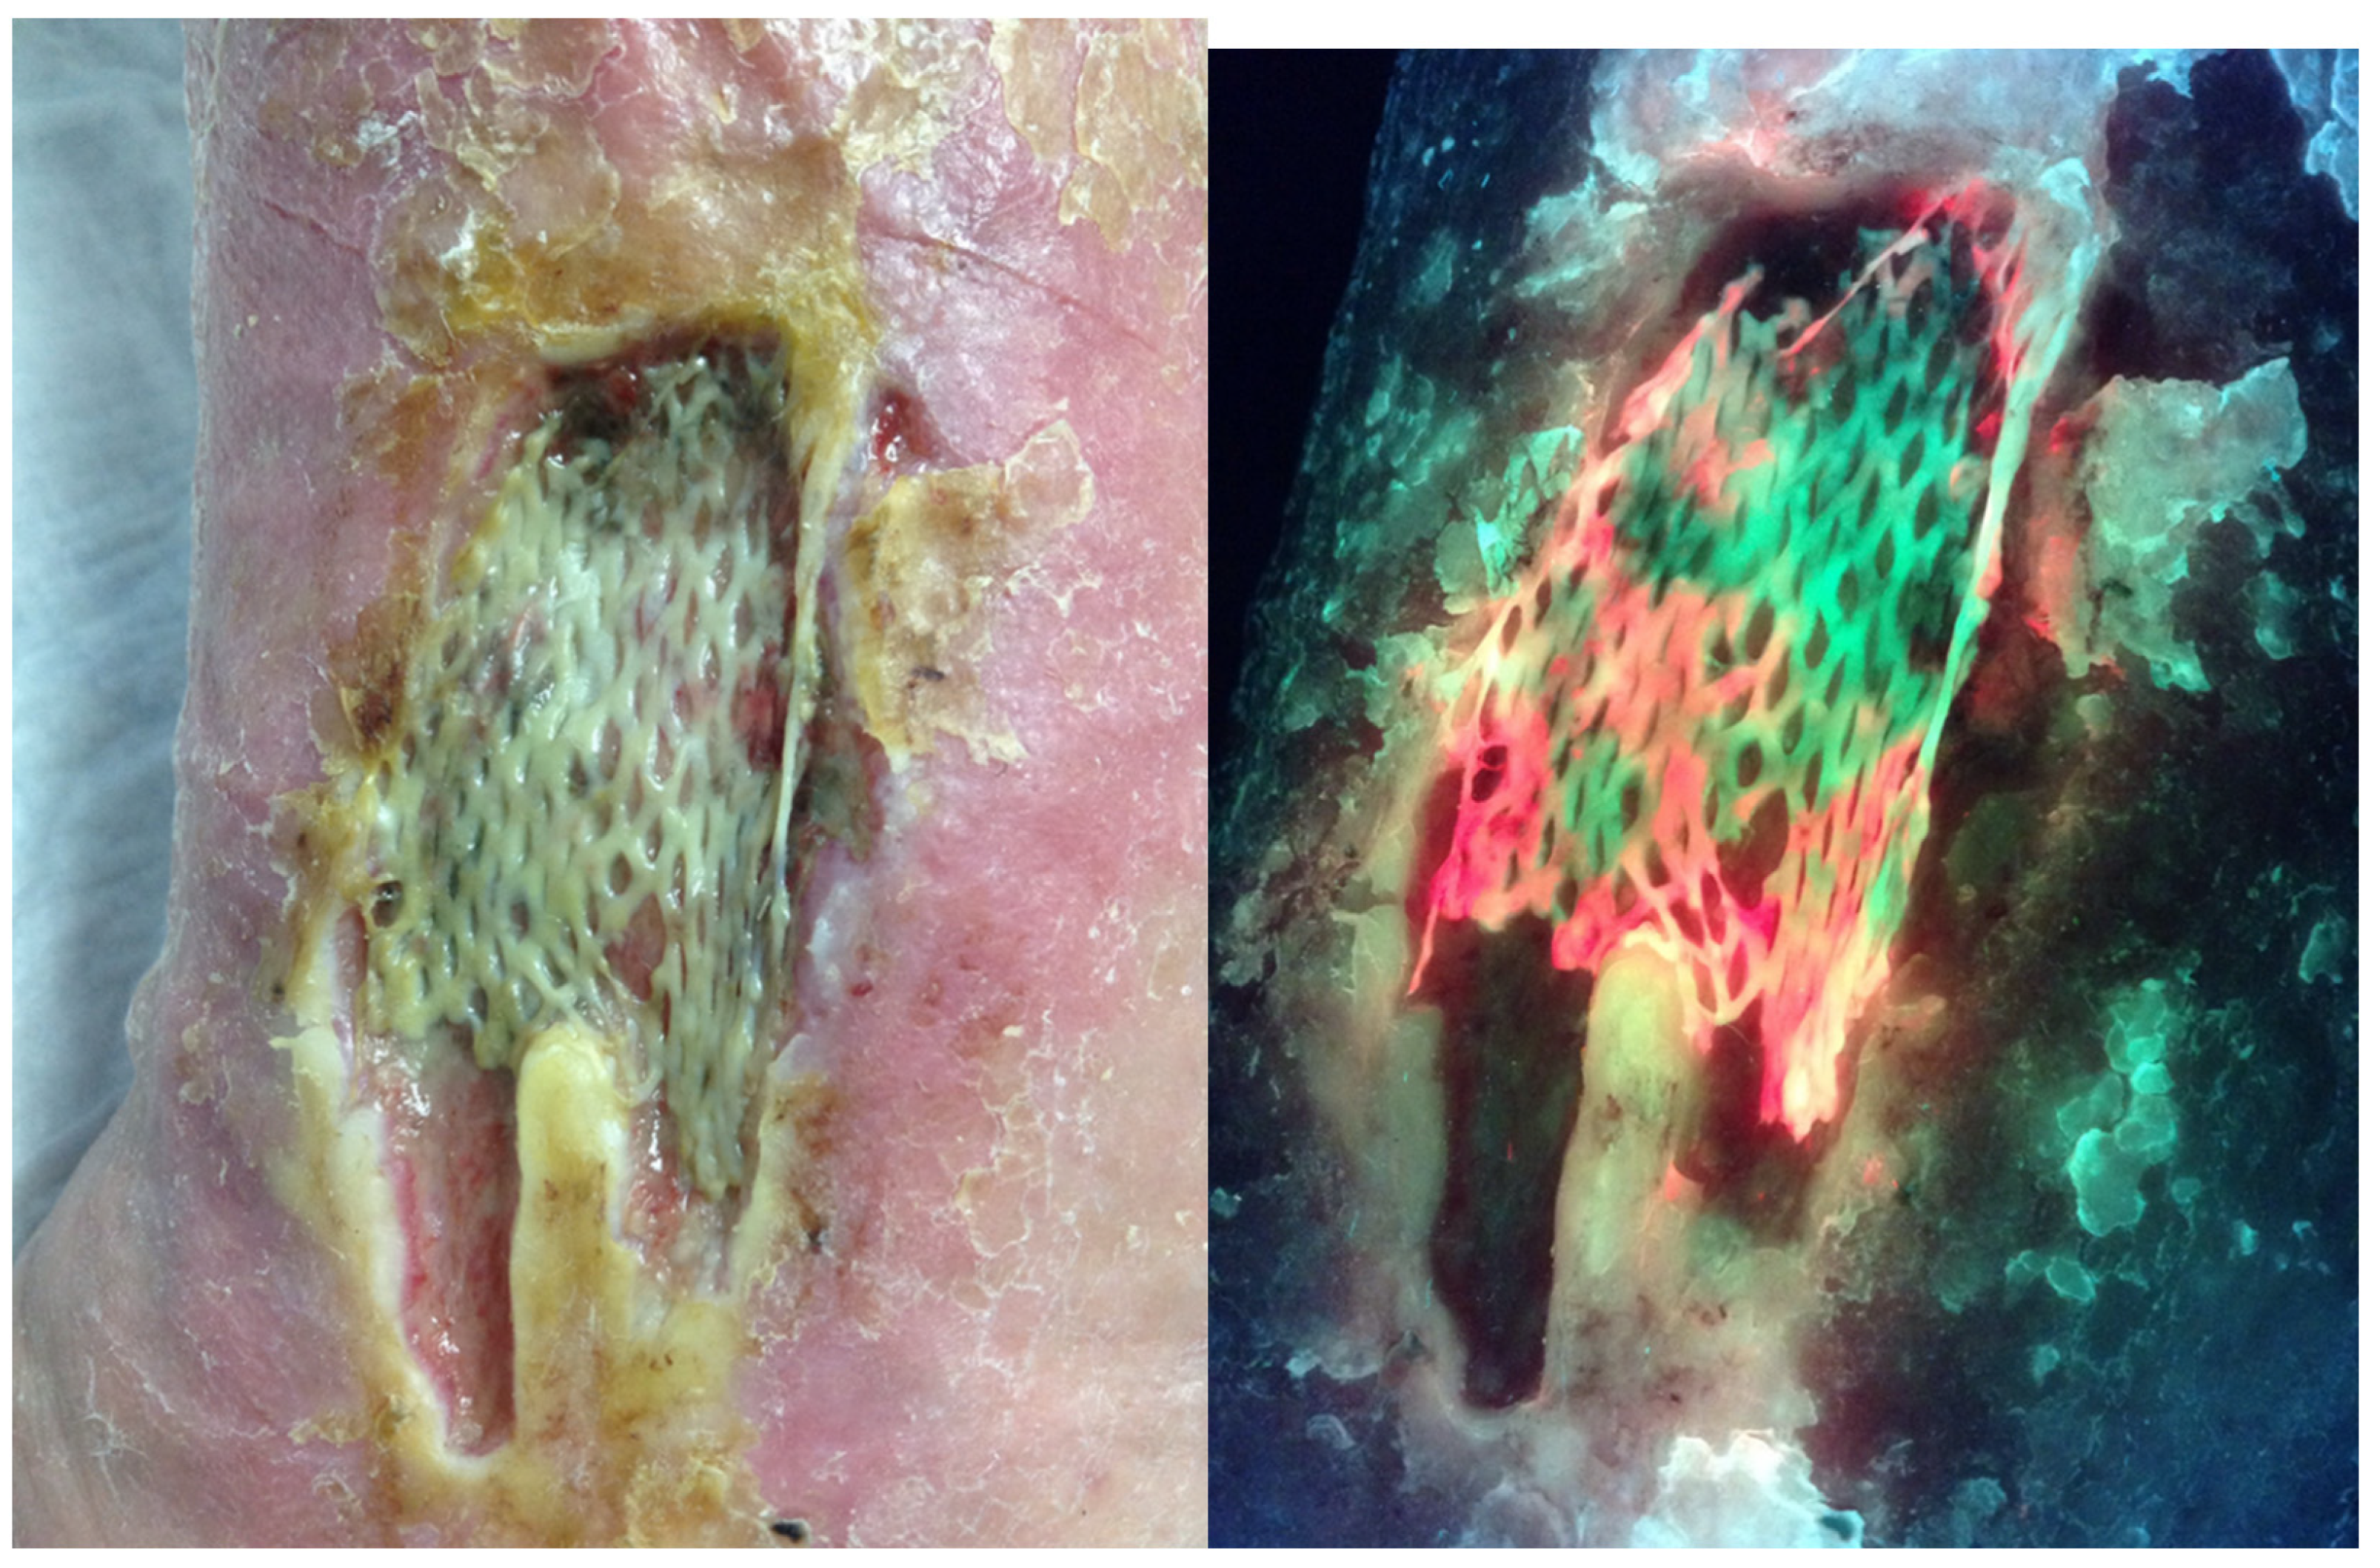

In a large multicenter clinical trial, investigators changed their antimicrobial treatment 42% of the time based on the fluorescence image (Figure 1) [18]. In some cases, debridement removed bacteria resulting in the absence of fluorescence on the post-debridement image (Figure 2). This was not true for all wounds that were debrided. It has also become clear that the use of the MLiX procedure as part of wound bed preparation could potentially reduce infectious complications associated with the application of cellular or tissue-based products (Figure 3).

Figure 3.

Standard and fluorescence images one week following application of a Cellular- and/or Tissue-Based Product (CTP) on a medical gaiter venous leg ulcer showing red fluorescence associated with the failure.